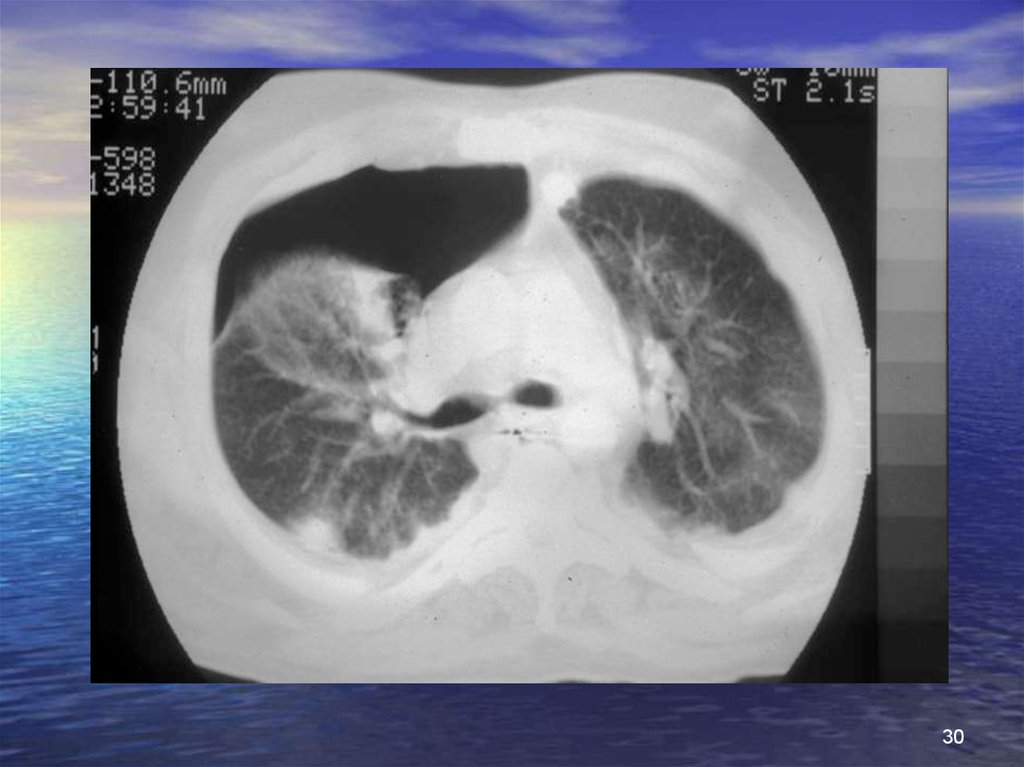

30.

30

Котузия легкого

Клиника

• Кровохаркание, отек легкого

Рентгенологическая картина

• Негомогенные затемнения

точечные или узловые

бронхограмма повышенной воздушности

Газы крови

• Гипоксемия

Гемостаз

• ДВС синдром

Развитие

• Спонтанное разрешение процесса в 24-72 часа

• Осложнения

инфекция бронхиальная, легочная

утечка воздуха

фиброз легких

41